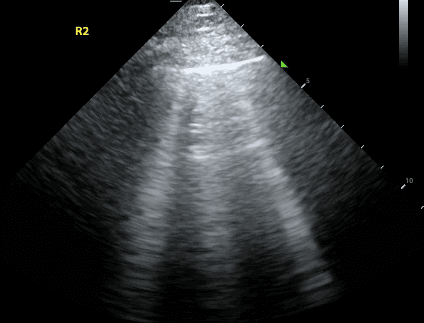

Lung sliding refers to the movement of the visceral pleura when it is directly adjacent to the parietal pleura. On lung ultrasound, it has been described as the appearance of “ants moving on a log” or “shimmering” of the pleural line.

In a pneumothorax, air separates the parietal and visceral pleura. Thus, you will not be able to see movement of the visceral pleura against the parietal pleura. The absence of lung sliding is very sensitive for the diagnosis of a pneumothorax. However, it is not specific as other pathologies such as pneumonia, ARDS, and bullae can all cause absent lung sliding.